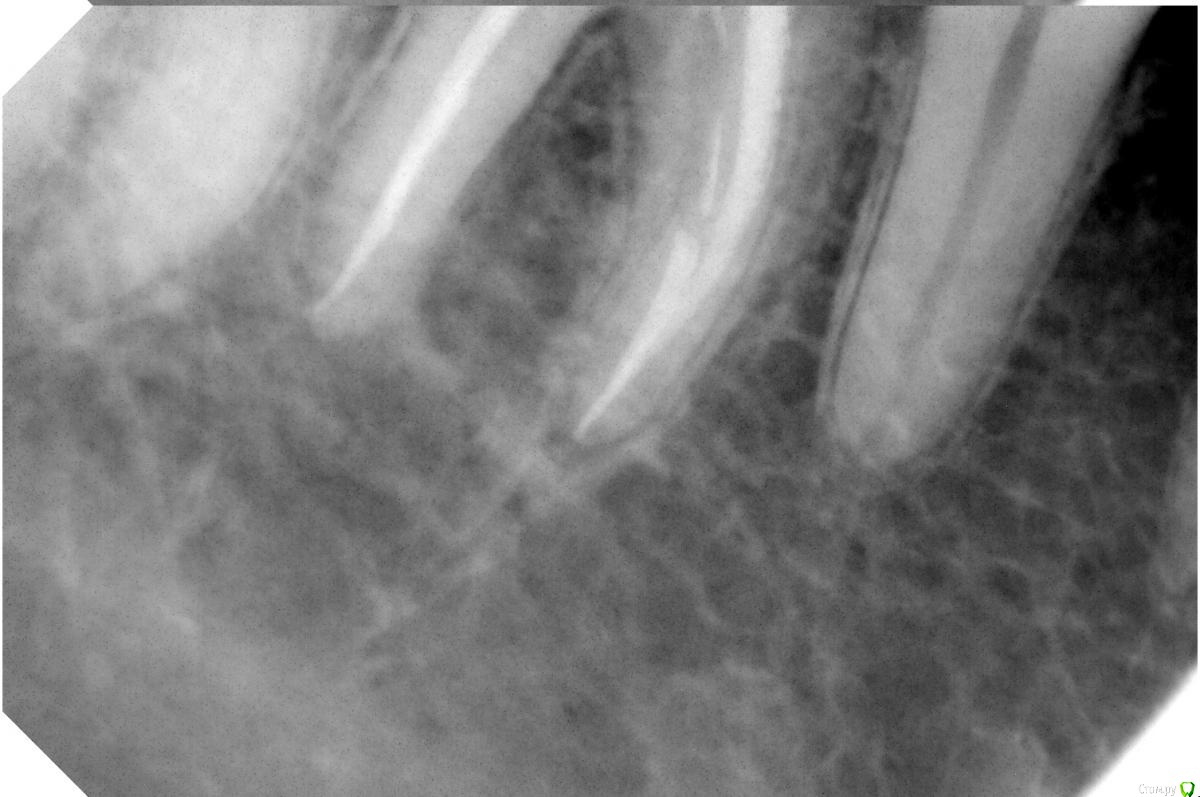

kot495 Опубликовано 8 сентября, 2016 Автор Поделиться Опубликовано 8 сентября, 2016 Привет! Спасибо за ответы. Мне предлагают еще такой вариант: каким-то образом разделить зуб на 2 части там где трещина, удалить патологически измененную ткань, и сделать на штифтах. Как считаете, возможно ли это в моем случае, и каков будет прогноз? Или обоснуйте удаление или другой вариант. Прилагаю снимки. Ссылка на комментарий

Bier Опубликовано 8 сентября, 2016 Поделиться Опубликовано 8 сентября, 2016 коронковой части зуба не видно. Не занимайтесь ерундой. Удалите зуб, если он подлежит удалению 3 Ссылка на комментарий